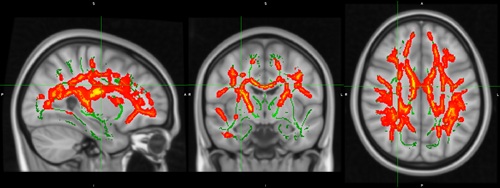

Imatges de ressonància magnètica cerebral que mostren les àrees de la matèria blanca on els canvis en inflamació cerebral associats al tractament antipsicòtic varien segons el consum previ de cànnabis

El nou estudi liderat per l'Institut de Recerca de l'Hospital del Mar ha fet servir per primera vegada una nova tècnica que mesura l'aigua lliure extracel·lular, marcador d'inflamació, en imatges cerebrals obtingudes amb ressonància magnètica de difusió per posar en evidència una associació del consum de cànnabis sobre la inflamació cerebral, un dels factors menys coneguts en la psicosi.

El treball ha analitzat imatges de ressonàncies magnètiques cerebrals d'un centenar de persones, tant pacients que havien patit un primer episodi psicòtic com voluntaris sans, mitjançant una nova tècnica que mesura l'aigua lliure extracel·lular. És el primer estudi que fa servir aquesta tècnica per estudiar l'efecte del consum de cànnabis en psicosi.